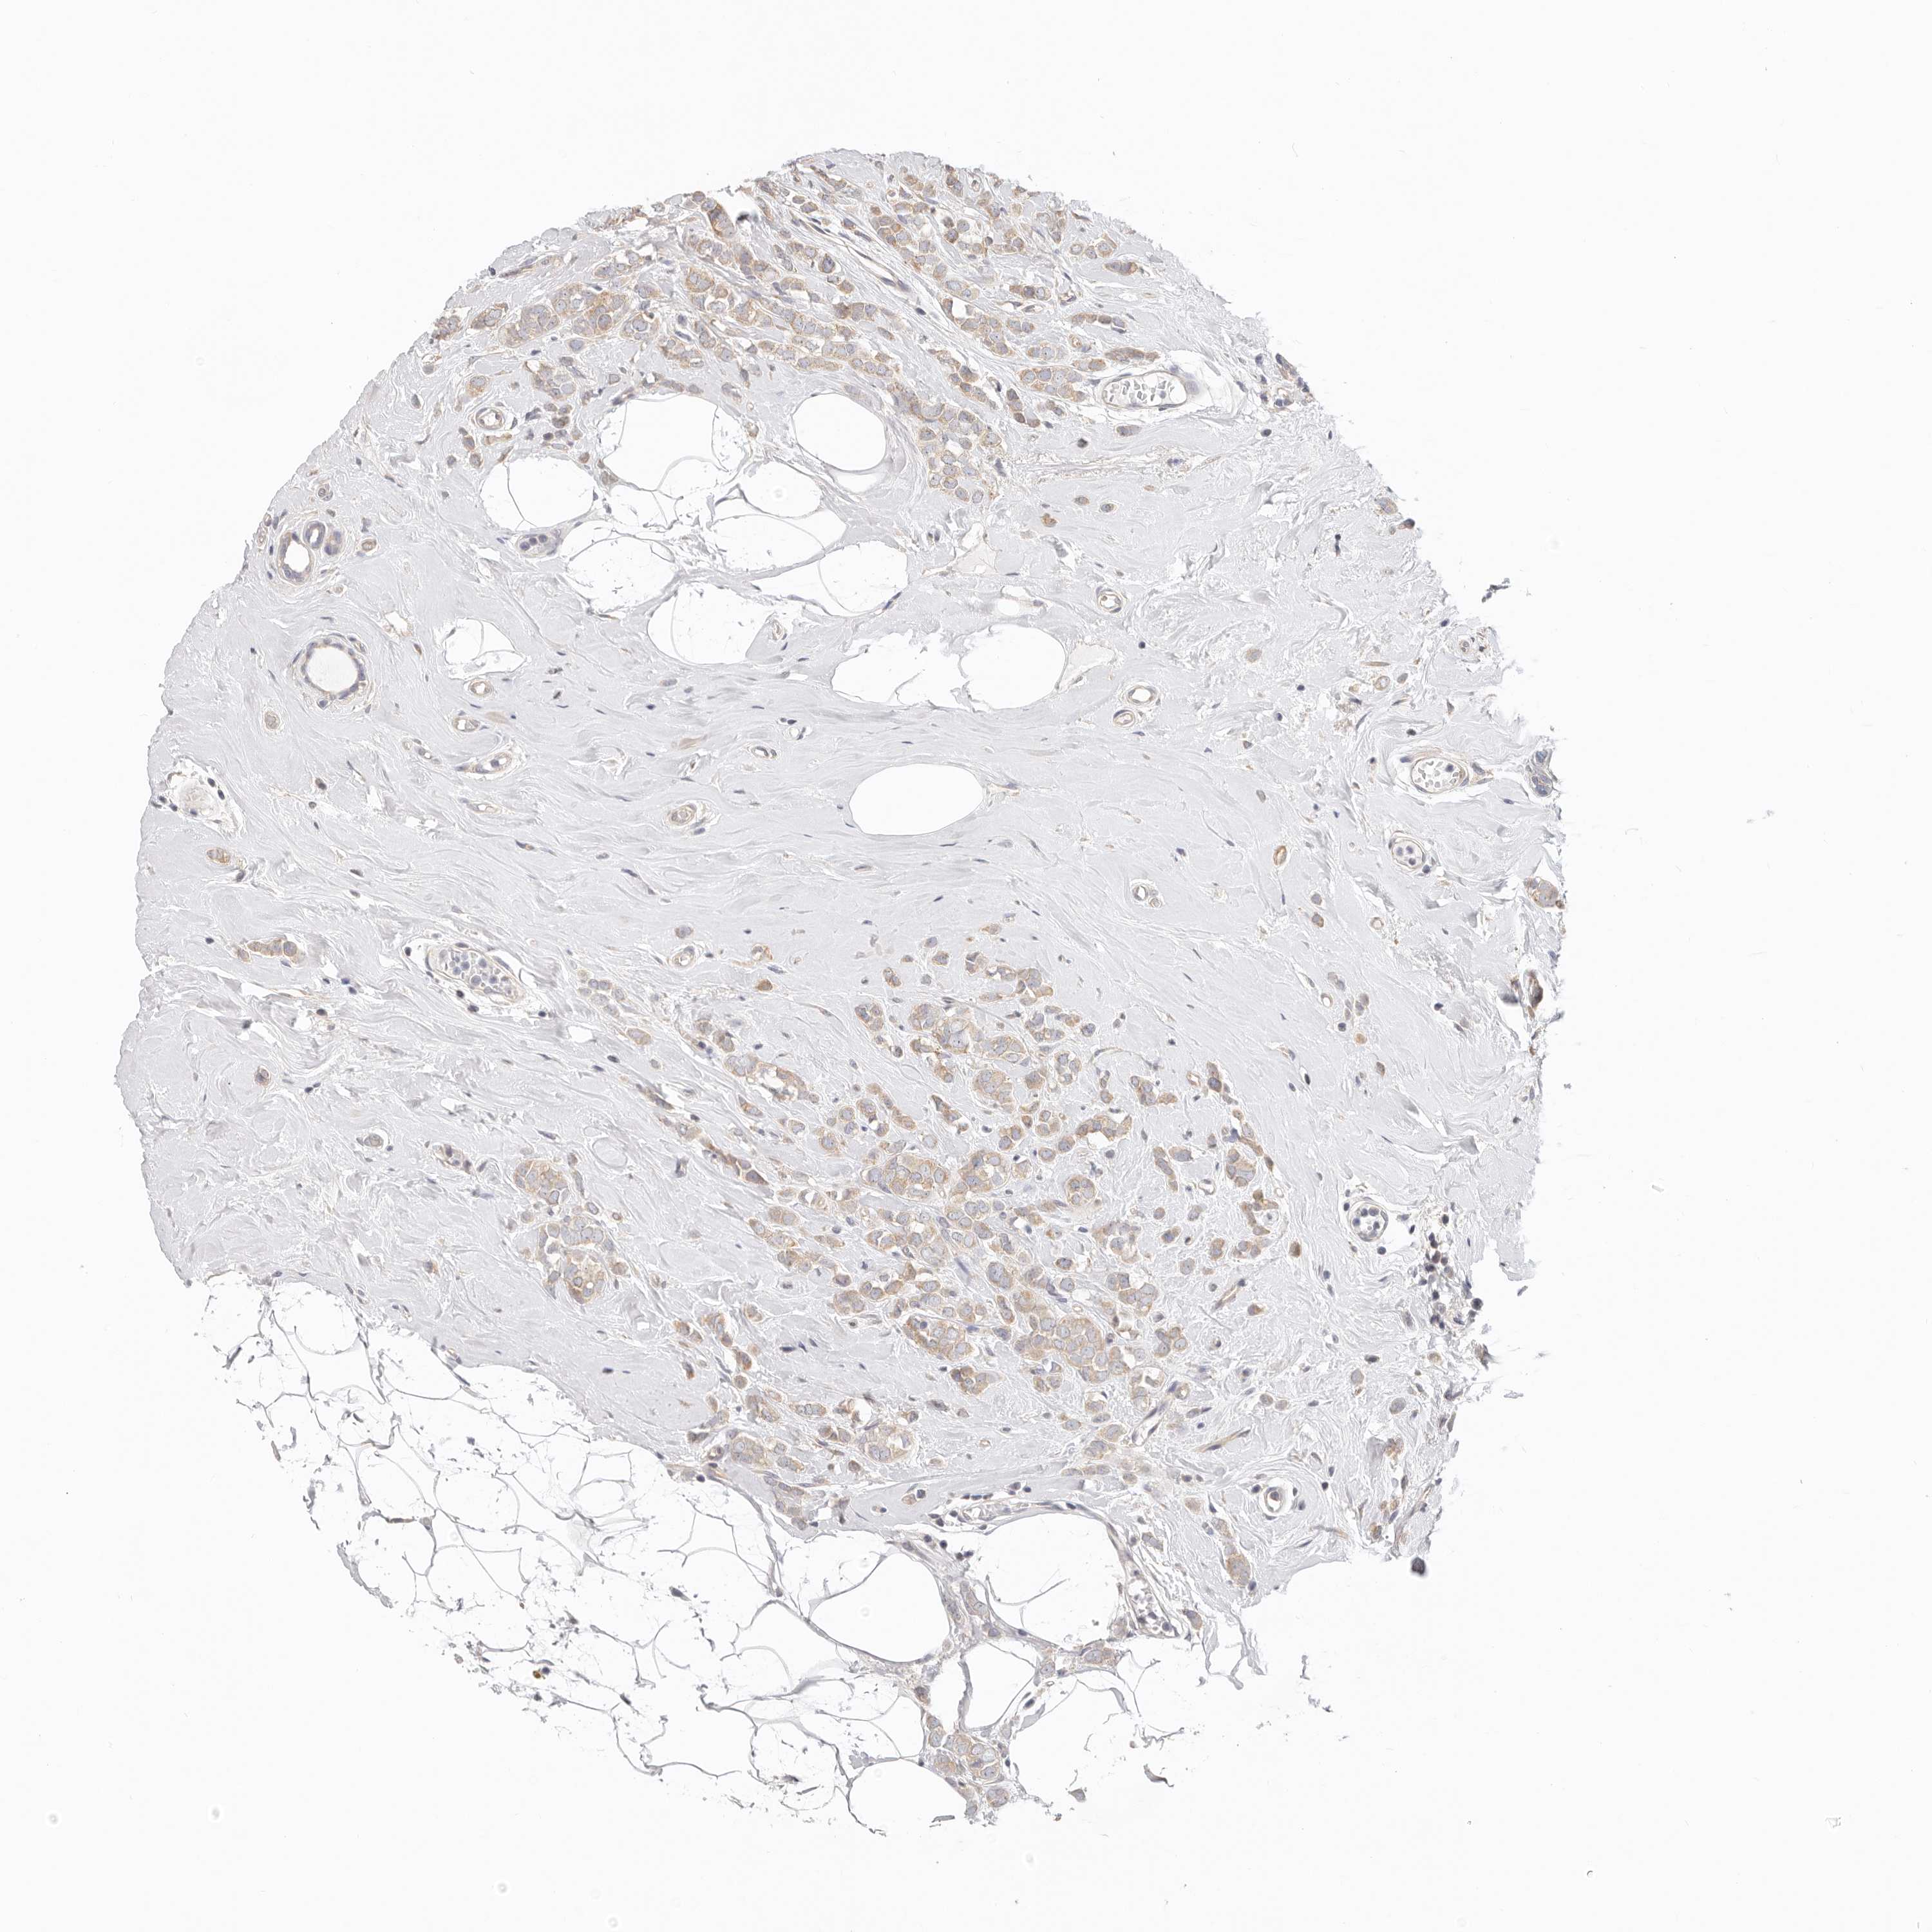

CANCER BREAST CANCER Show tissue menu

BRCA TCGA BRCA VALIDATION PROTEIN EXPRESSION

Breast cancer

Human cancer